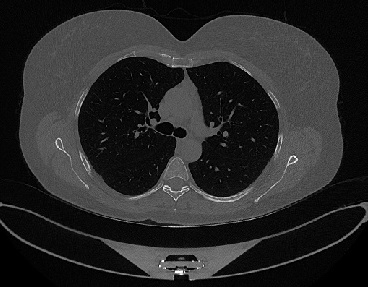

Figure 1 shows four CT scan slices, two from a non-COVID-19 CT scan, on the left and two from a COVID-19 scan, on the right. Bilateral ground glass regions are seen especially in lower lung lobes in the COVID-19 slices.